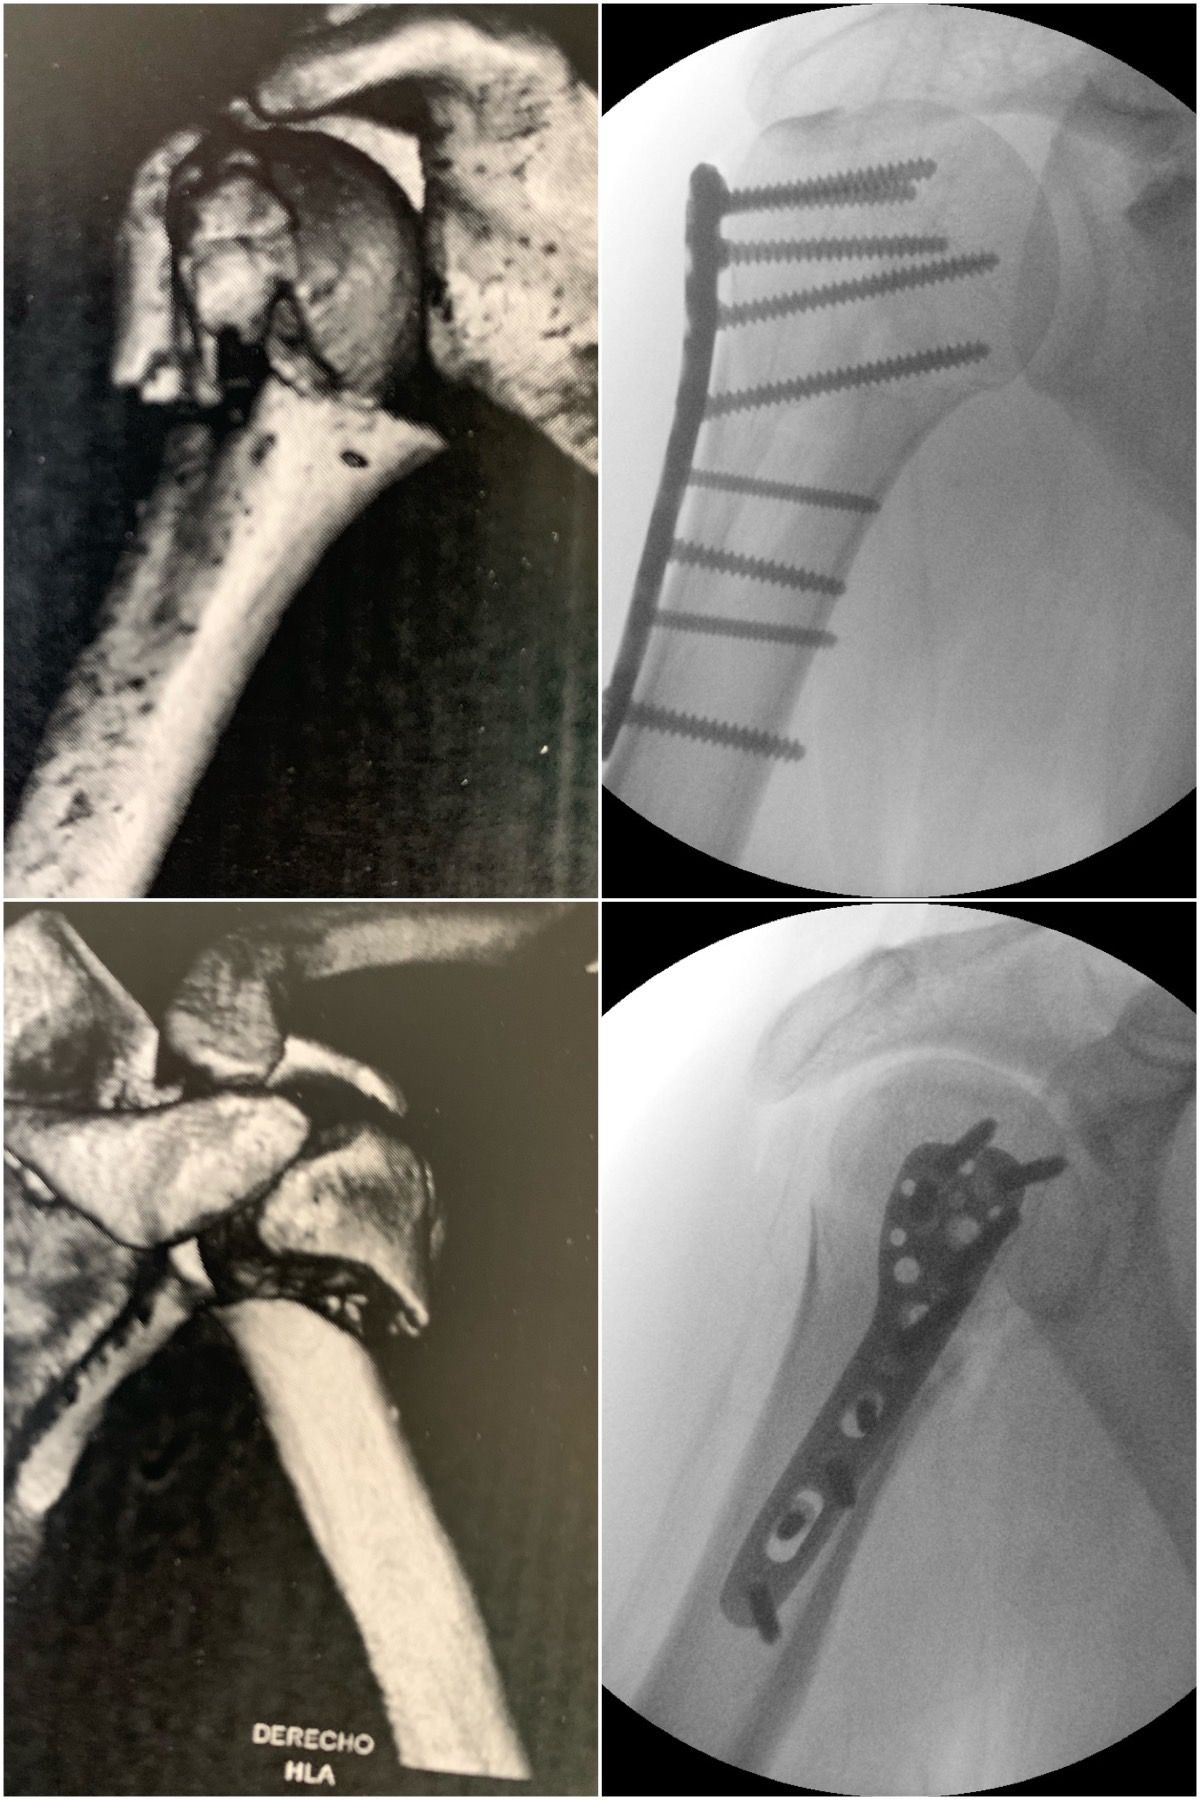

Se especializa en Síndrome del Manguito Rotador, Artroscopía de Hombro, Luxación de Hombro, Epicondilitis Lateral (Codo de Tenista), Fractura de Clavícula, Disyunción Acromioclavicular, Fracturas de Codo.

Conferencista. Tríada Terrible del Codo. II Jornadas de Traumatología. Hospital Universitario de Caracas (HUC). Caracas, Venezuela. 2015